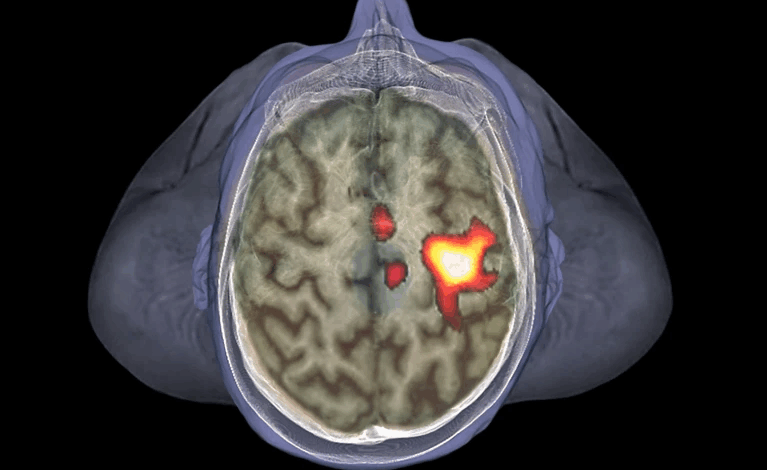

Os cientistas descobriram que a aproximação de um avatar infeccioso ativava áreas do cérebro ligadas ao espaço pessoal — a região imediatamente ao redor do corpo. Em seguida, houve um aumento repentino na “rede de saliência” do cérebro: um conjunto de regiões envolvidas no reconhecimento de eventos importantes, incluindo ameaças, e na resposta a elas.

Essa atividade cerebral desencadeou um aumento na frequência de defensores imunológicos chamados células linfoides inatas, que fazem parte da primeira linha de defesa do corpo contra invasores. A frequência dessas células foi maior em participantes abordados por avatares infecciosos do que naqueles abordados por controles. A atividade imunológica naqueles abordados por avatares infecciosos refletiu a dos participantes que receberam a vacina contra a gripe .